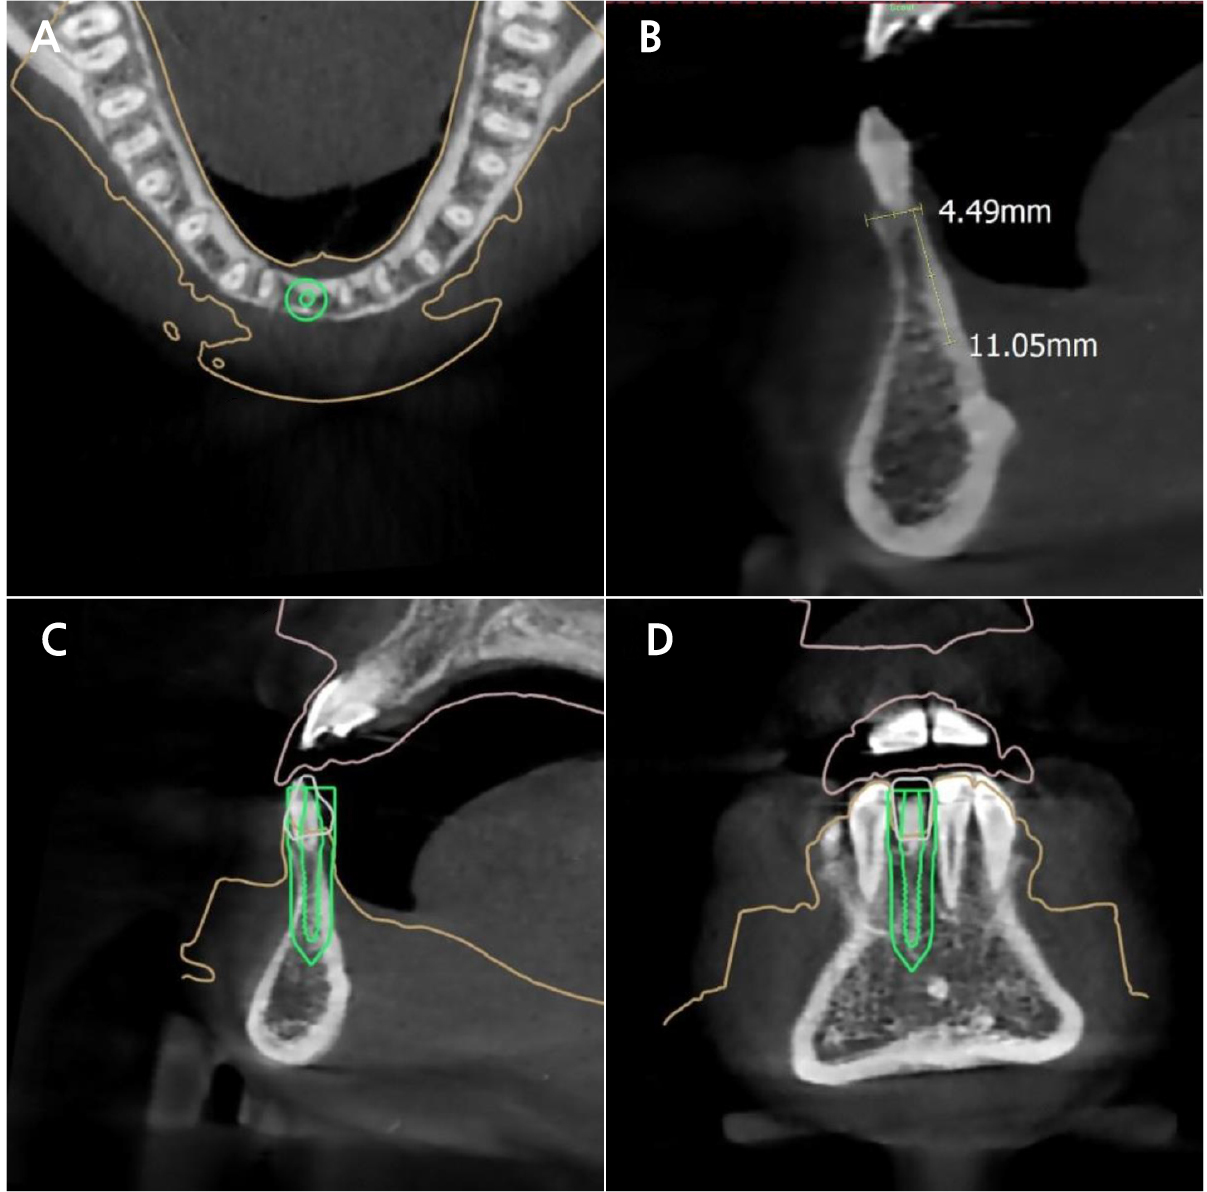

Cone-beam computed tomography imaging was performed to evaluate bone width. The site of interest showed a narrow width, which is incapable of regular-diameter implants. Therefore, a one-piece mini-implant (MS Narrow Ridge; Osstem, Busan, Korea) with a diameter of 2.0 mm, length of 10 mm, and gingival height of 4 mm was planned for placement (Fig. 2). A computer-designed surgical guide was manufactured by an implant company (OneGuide; Osstem, Busan, Korea).

Another consideration is the lack of a platform structure for one-piece implants. The endo-osseous and transgingival portions of the one-piece implant were connected mechanically. Hence, the position of the transgingival portion in relation to the underlying bone was determined solely during the placement stage.13 Therefore, a computer-designed stereolithographic surgical guide was used in our case. Additionally, because the transmucosal portion of a one-piece implant is unchangeable, it is important to harmonize the emergence profile of the restoration and the transmucosal portion of the implant. To ensure such results, we fabricated a working cast using a laboratory analog with a detachable gingival mask.